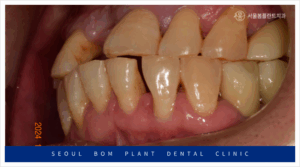

앞니 외에도 치료가 필요한 부위가

많이 있었는데요.

빨간색 동그라미 표시의

위턱 왼쪽 첫 번째 큰 어금니(#26)와

아래턱 왼쪽 작은 어금니(#34,35)

아래턱 오른쪽 첫 번째 큰 어금니(#46)가

뿌리 끝 염증과 함께 동요도도 심한 상태라

발치가 불가피한 상황이었습니다.

양측 어금니의 상실로

저작이 되지 않고 있다 보니

앞니에 무리가 많이 가는 상황으로

어금니의 수복이 시급했는데요.